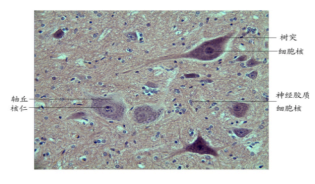

在《组织学与胚胎学》实验教学中,课程组采用显微镜图像采集系统将不同视野下的组织学切片典型结构拍照采集,并使用图像处理软件加注标示,使学生能清晰直观的观察到镜下影像,实现了认知器官和组织微细结构的学习目标。

教师使用图像处理软件制作的组织学切片 教师使用制作的组织学切片图开展课堂讨论

在病理学线上实验教学中,选取丰富实验教学资源,并上传线上教学平台,学生通过课前预习病理学资源库的实验课程视频,教师通过使用显微镜室的光学显微镜采取显微摄影技术拍摄真实的镜下图像,通过云课堂头脑风暴和讨论等形式将镜下图像上传网络,让学生认真观察后,说出病变并指认结构,达到了与在实验室现场观察一样的真实效果。结合数字切片讲解视频让学生掌握病变内容,线上课程群讲解结合病例分析完成实验课在线教学。

显微摄影技术拍摄的镜下图像 头脑风暴 职教云平台线上实验视频